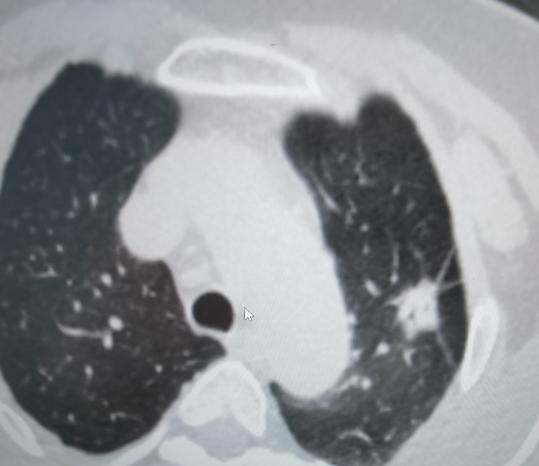

如果检查报告上提到结节有“分叶”或者“毛刺”这样的描述,确实要提高警惕。这两种形态经常被看作是“危险信号”,因为恶性肿瘤(图1)的生长方式往往不太规则,容易形成分叶状的轮廓,或者像螃蟹脚一样向外伸出毛刺,侵犯旁边的正常组织。

不过,也不是说有这些表现的就一定是癌。有些良性结节(图2),比如因为结核感染引起的“结核球”,或者长期慢性炎症形成的“炎性假瘤”,也可能看起来有分叶或毛刺。所以光看这一个特征,还不能直接下定论。